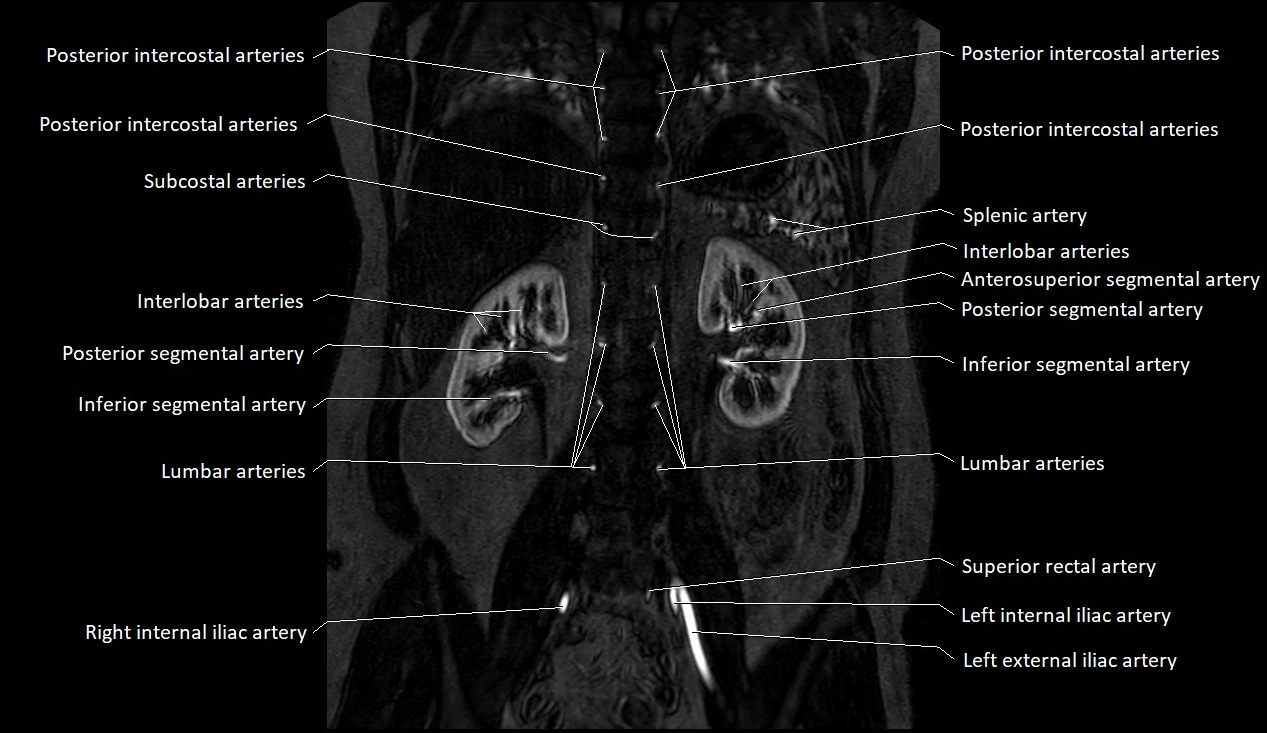

The abdominal aorta is the continuation of the thoracic aorta, beginning at the level of the aortic hiatus of the diaphragm (T12 vertebra) and terminating at the level of the L4 vertebra where it bifurcates into the right and left common iliac arteries. It lies slightly to the left of the midline and courses anterior to the vertebral bodies, surrounded by the retroperitoneal structures of the abdomen.

The abdominal aorta gives off numerous visceral and parietal branches, supplying the abdominal organs, pelvic structures, and lower limbs. It is the main conduit of oxygenated blood from the heart to the abdomen and lower body. The aorta is clinically significant as the common site of aneurysm, dissection, atherosclerosis, and traumatic injury.

Branches

• Unpaired visceral branches: celiac trunk, superior mesenteric artery (SMA), inferior mesenteric artery (IMA)

• Paired visceral branches: middle suprarenal arteries, renal arteries, gonadal arteries (testicular or ovarian)

• Parietal branches: inferior phrenic arteries, lumbar arteries, median sacral artery

• Terminal branches: right and left common iliac arteries

MRA (Magnetic Resonance Angiography):

• Contrast-enhanced MRA provides high-resolution imaging of the aorta and its branches

• Allows 3D reconstruction of visceral, parietal, and terminal branches

• Excellent for evaluating aneurysm size, dissection flap, stenosis, or preoperative planning

• Non-invasive alternative to conventional angiography

MRI images

image